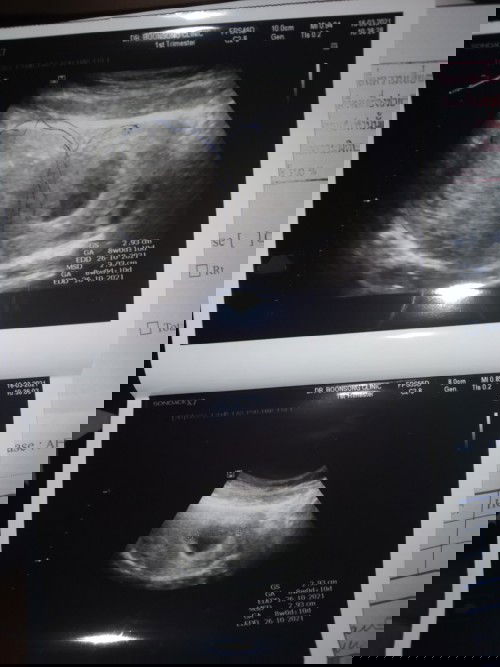

ผิดหวังมากเลยค่ะ

ท้องสองแล้วค่ะที่เป้นแบบนี้ แม่ๆคิดว่ายังมีหวังที่จะเห้นตัวน้องไหมคะ #ผิดหวังมาก😔😔 #่ขอประสอบการแม่ๆเคยเจอมาหน่อยค่ะ😔🙏